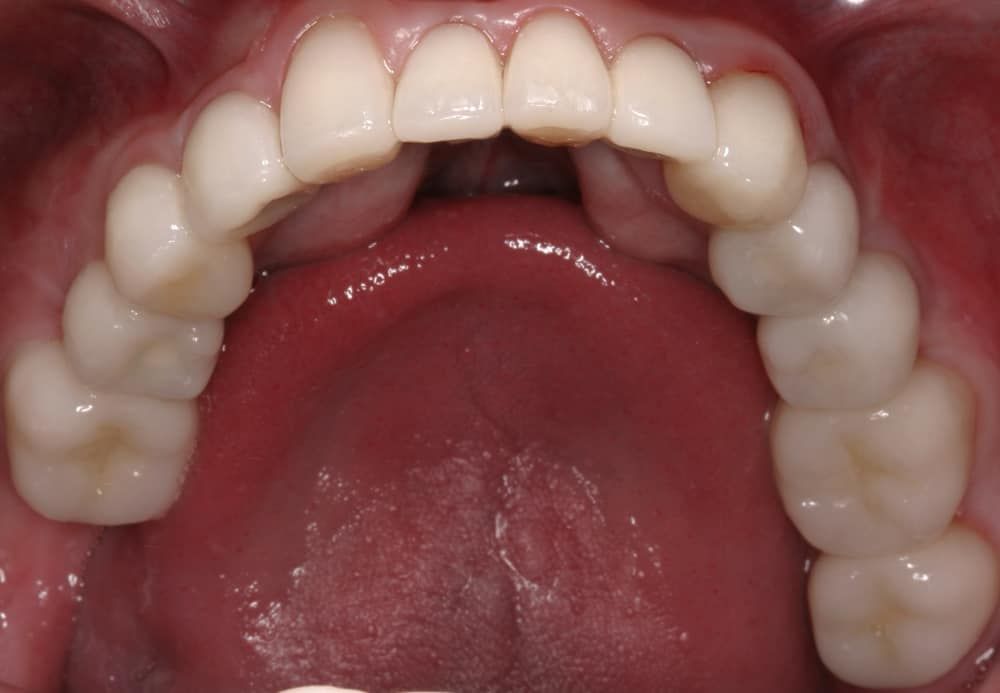

After:Â Implants were then placed by the team oral surgeon utilizing surgical guides fabricated by Dr. Leopardi. Dr. Leopardi then performed a complete dental (full mouth) rehabilitation: full coverage, conservative bonded porcelain restorations on natural teeth; all ceramic implant restorations on the upper lateral incisor implants (sited 7 and 10), porcelain fused to gold implant restorations on implants 3, 14, 19, 21, 23, 25, 28 and 29, at increased occlusal vertical dimension. Patient was restored to full function and aesthetics, significantly improving quality of life.